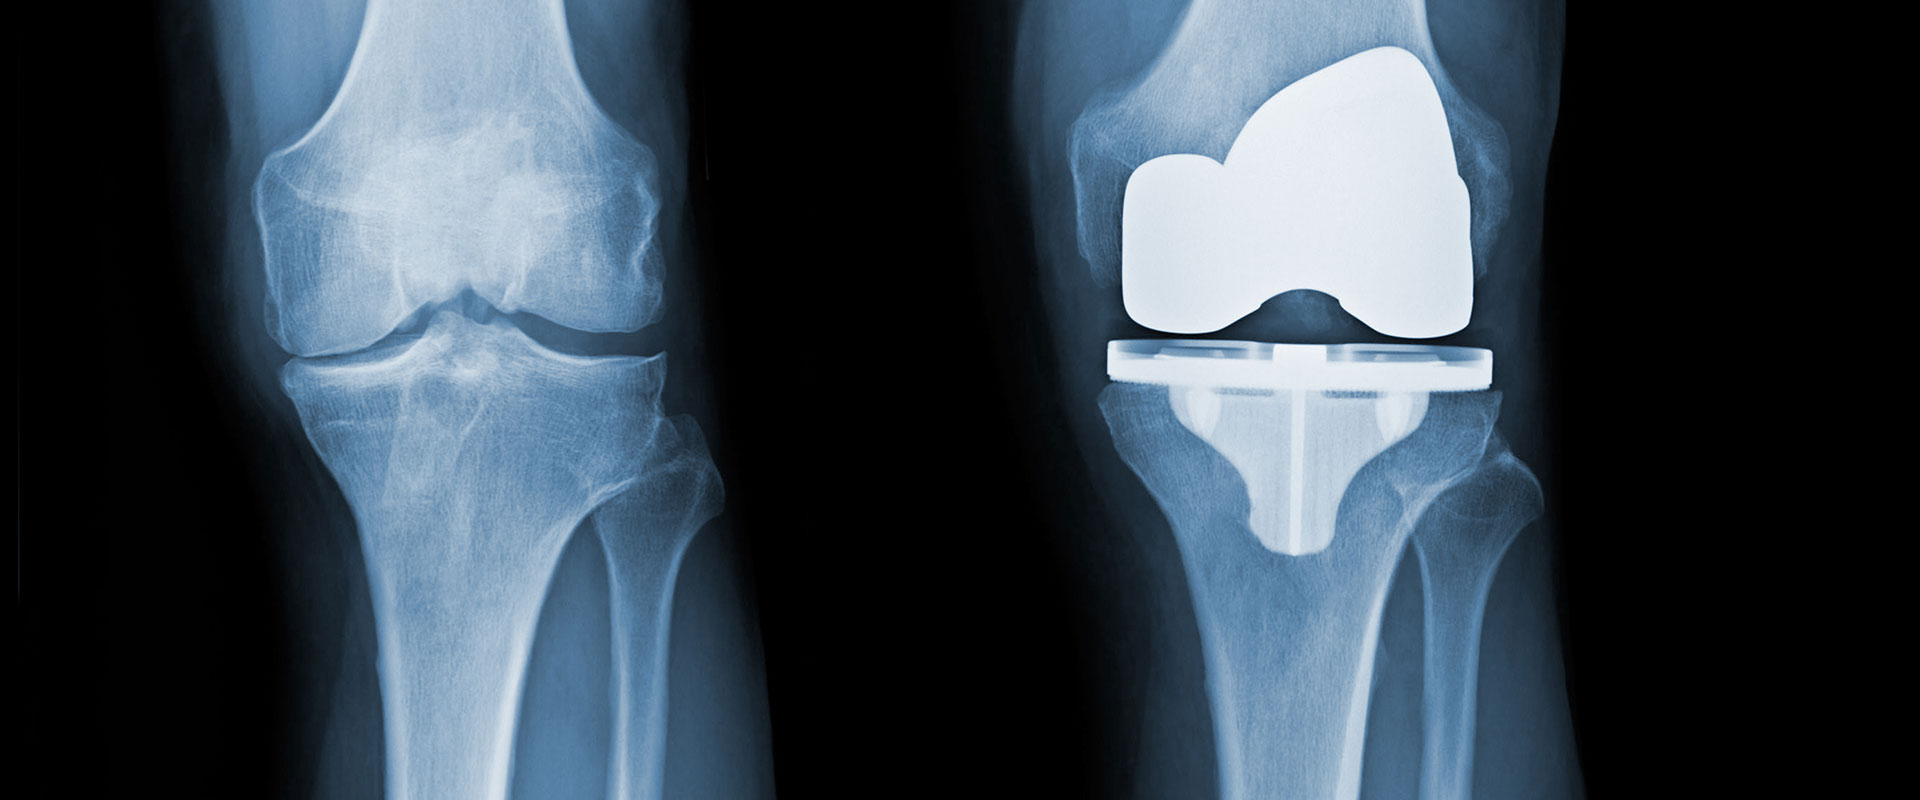

Joint replacements can restore some or all of a person’s lost mobility. These replacements are made of metal or plastic, and they’re surgically implanted inside patients’ bodies to replace the parts of their joints that were weakened or damaged.

Around 800,000 knee replacement surgeries are performed annually in the U.S., and the number of those procedures is increasing every year. As with hip replacement surgeries, people who get knee replacements are at risk of suffering serious complications if their replacements fail.